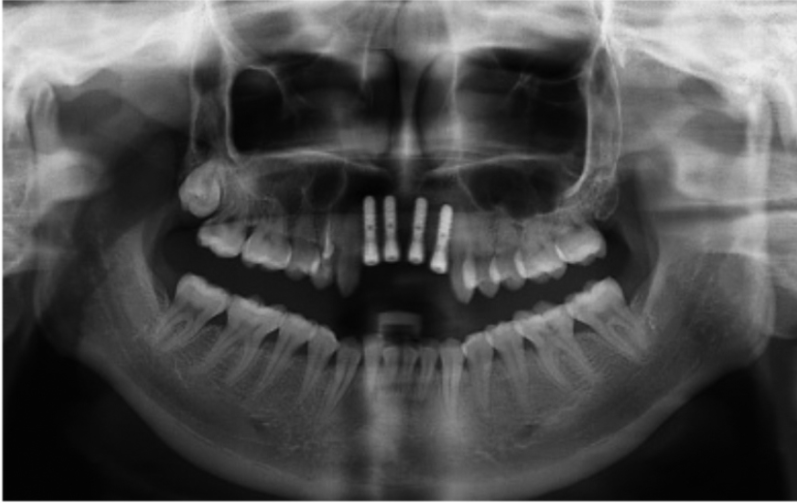

图1 术前全景片显示A1B2缺失

图2 术后全景片A1B2种植术后

图3 术前全景片

图4 同一患者术后全景片

图5 术前全景片

图6 术后全景片

首先在进行临床检查时,可以观察到缺牙区的宽度和厚度,用手指扪诊时前庭沟骨质没有明显的凹陷,这种情况可以拍摄牙片了解牙槽骨状况及与鼻腔的距离。由于牙片显示的范围有限,最好能够拍摄全景片了解邻近结构的情况,比如邻牙的情况、鼻腔底的距离,切牙孔的大小与位置等等。